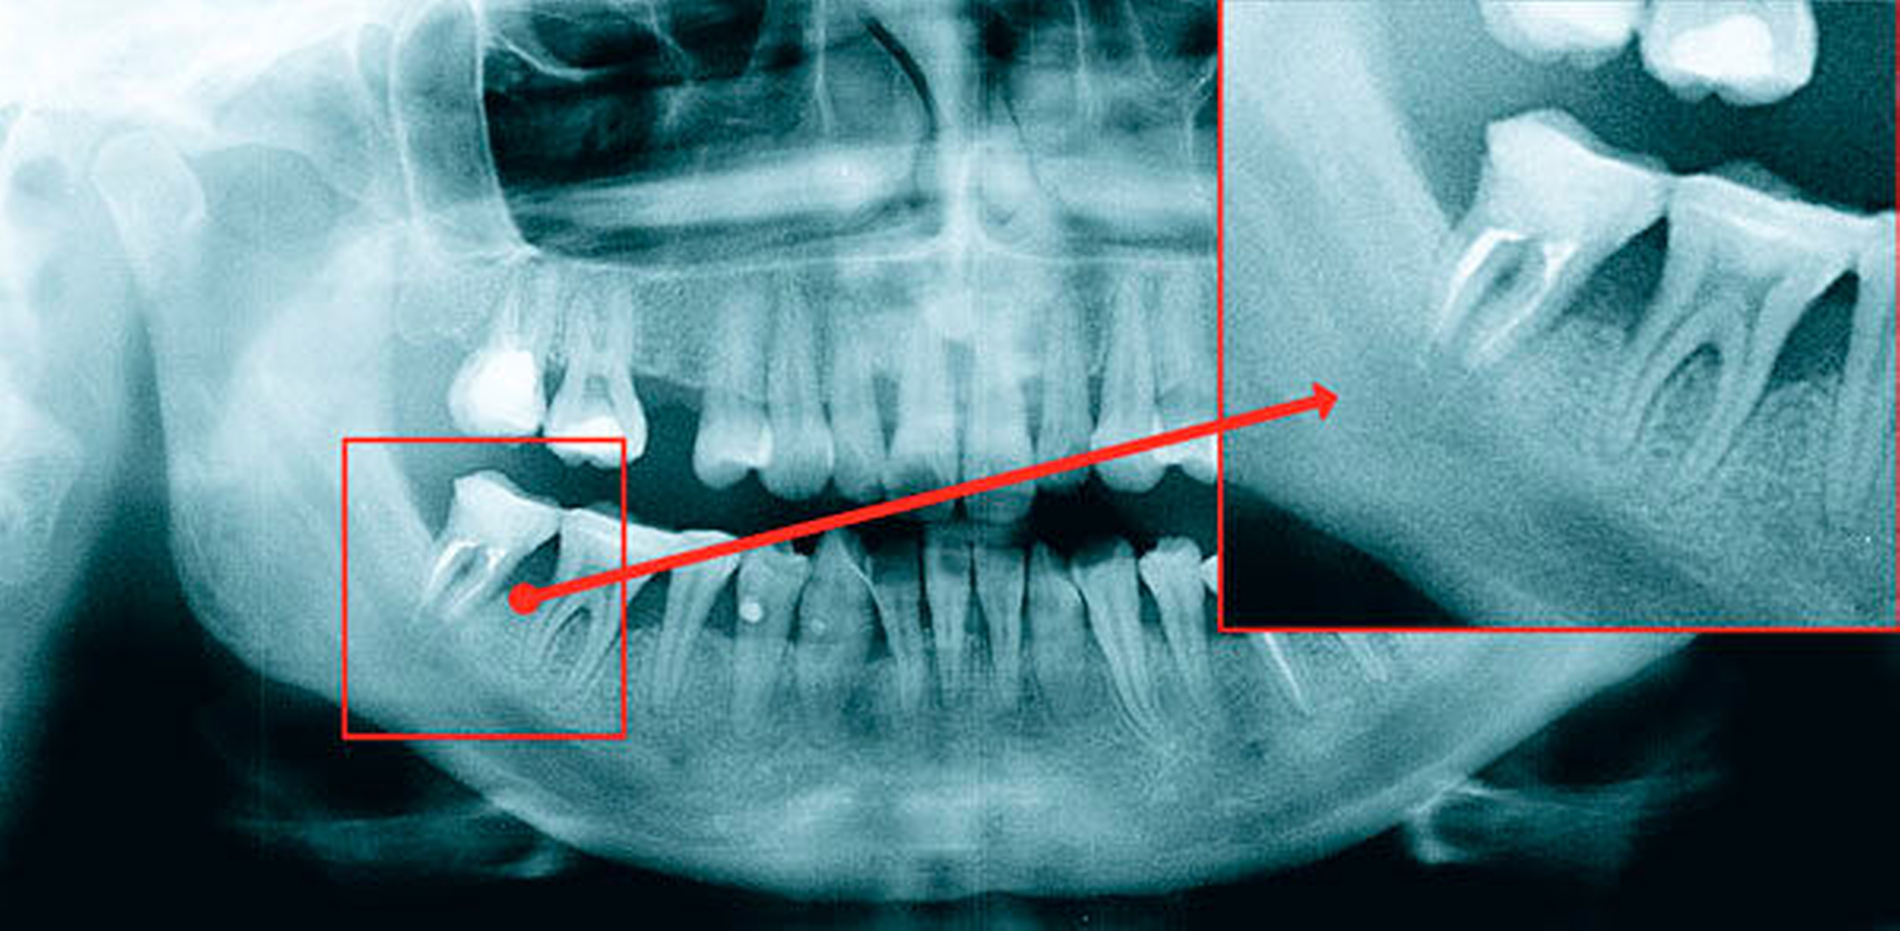

Der Nervus trigeminus, der fünfte Hirnnerv, ist der größte peripher-sensorische Nerv des Körpers. Er versorgt sensibel das Gesicht, die Augen, den Mund und den Skalp über seine drei peripheren Äste (Nn. ophthalmicus, maxillaris, mandibularis). Ebenso innerviert er die Kaumuskulatur. Periphere Schädigungen des Nervus trigeminus können bei vielen invasiven zahnärztlichen oder zahnärztlich-chirurgischen Eingriffen auftreten (Abbildung 1) [Kämmerer PW et al., 2015]. Von iatrogenen Schäden nach invasiven zahnärztlichen Eingriffen sind vor allem der Nervus lingualis (lose im Weichgewebe im lingualen Unterkieferseitenzahngebiet) und der Nervus alveolaris inferior (in seinem knöchernen Kanal beziehungsweise vor seinem Eintritt ins Foramen ovale) betroffen.

Leider gibt es keine Möglichkeit, Nerven nach außen wirksam darzustellen; daher ist eine explorative Operation erforderlich, und die Behandlungsentscheidung muss getroffen werden, während sich der Patient auf dem Operationstisch befindet [Kushnerev E, Yates JM, 2015]. Es gibt eine Reihe von Methoden, um Nervschäden zu reparieren. So kann je nach Bedarf gewählt werden zwischen externer Dekompression des N. alveolaris inferior (Abbildung 3) [Bagheri SC et al., 2012] , direkten Nervnähten [Cornelius CP et al., 1997] und der Rekonstruktion mit autologen Transplantaten (Nerven (N. suralis / N. aurikularis magnus) oder Venen) [Cornelius CP et al., 1997; Pogrel MA, Maghen A, 2001]. Weitere Möglichkeiten bestehen in der Anwendung von allogenen Manschetten um den beschädigten Nerv sowie in der großflächigen Freilegung, Mobilisation (Abbildung 4) und Readaptation der Nerven.